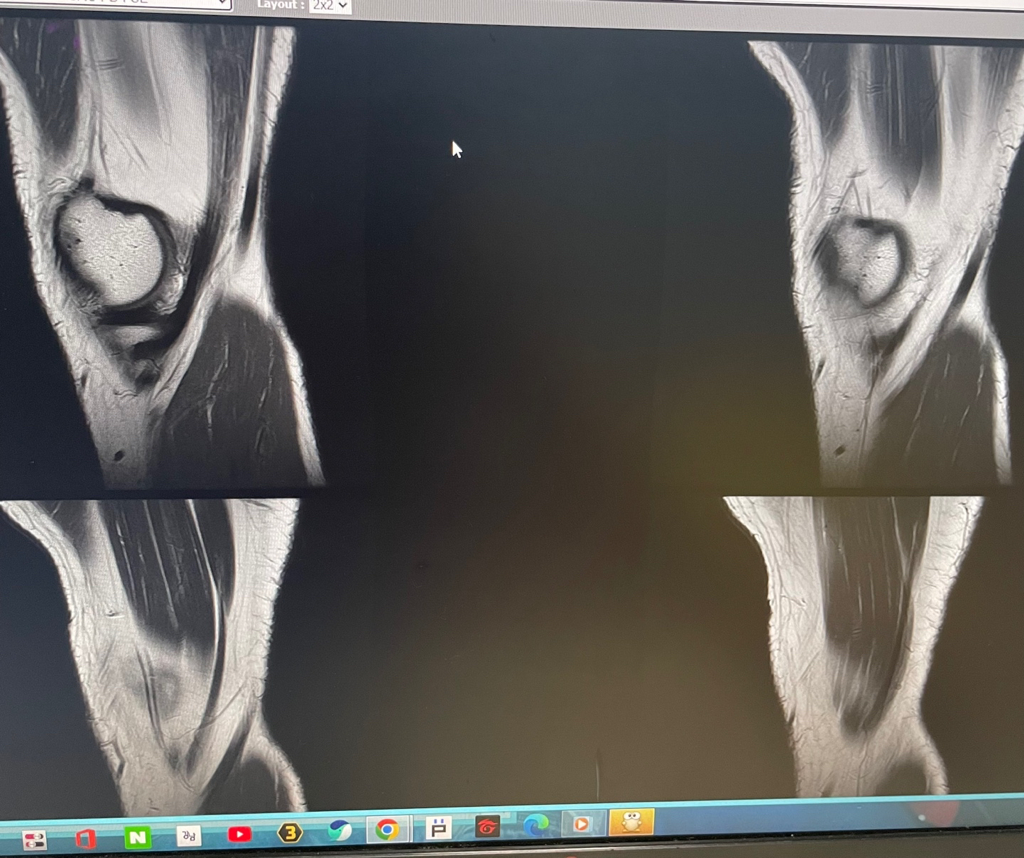

무릎 mri 원형원골인지 봐주실 수 있을까요

무릎이 너무 자주 아파서 mri를 찍어봤는데 무릎 연골에 이상이 있을까요

무릎이 선천적으로 원형연골인지 봐주시면 감사하겠습니다

MRI 판독에는 퇴행성 연골 손상, 바깥쪽 원판형 반월상 연골 이 의심된다고 적혀 있습니다.